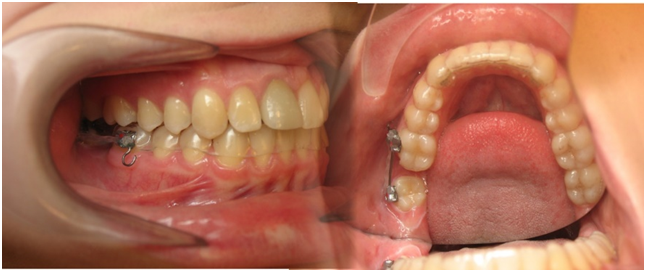

Nhắc đến nắn chỉnh răng hay chỉnh nha mọi người đều nghĩ nó chỉ giúp ích cho những trường hợp răng hô, móm hoặc khấp khểnh, nhưng nhiều trường hợp mất răng, chỉnh nha cũng có thể thay thế răng đó bằng một răng thật mà không cần phải trồng răng giả.